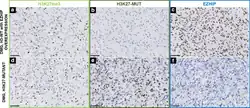

Histologie

In der Lichtmikroskopie zeigen sich diffus in das umliegende Gewebe infiltrierende Tumorzellen. Es finden sich viele Mitosen und teilweise auch mikrovaskuläre Proliferation und Nekrosen.[1]

Immunhistochemie

Durch immunhistochemische Verfahren können spezifische Proteine sichtbar gemacht werden.

Wie andere Gliome exprimieren DMGs üblicherweise OLIG2-, MAP2- und S100-Proteine, manchmal auch GFAP. Beim EGFR-mutierten Typ ist eine GFAP-Expression meist vorhanden, die von OLIG2 kann jedoch fehlen. Alle DMGs zeigen eine verringerte Anfärbung von H3K27me3. Durch die Anfärbung von H3K27M und EZHIP ist es möglich, zwischen Subtypen zu differenzieren.[1]